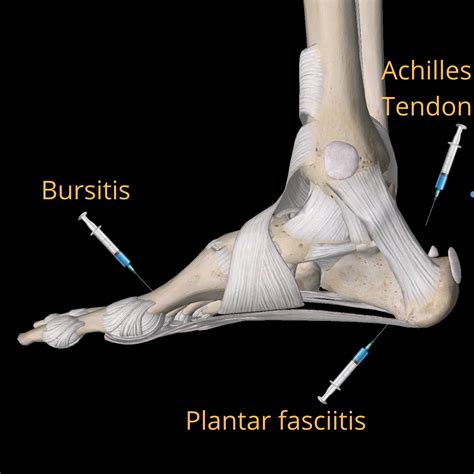

Plantar fasciitis is a common condition that causes heel pain and discomfort, often due to inflammation of the plantar fascia, a thick band of tissue that runs along the bottom of the foot. While there are various treatment options available, one of the more effective methods for managing severe cases is a plantar fascia injection. This procedure involves injecting a corticosteroid or other medication directly into the affected area to reduce inflammation and alleviate pain.

Plantar fasciitis is characterized by pain and stiffness in the heel, often worse in the morning or after prolonged periods of rest. The condition is typically caused by repetitive strain on the plantar fascia, which can occur due to activities like running, standing for long periods, or wearing improper footwear. Risk factors include obesity, high arches, and tight calf muscles.

A plantar fascia injection is usually considered when conservative treatments, such as rest, ice, compression, elevation (RICE), physical therapy, and over-the-counter pain relievers, have not provided sufficient relief. The injection can be a game-changer for those experiencing chronic pain and limited mobility due to plantar fasciitis.

There are several types of injections that can be used to treat plantar fasciitis, each with its own benefits and considerations:

• Corticosteroid Injections: These are the most common type of plantar fascia injection. Corticosteroids are powerful anti-inflammatory medications that can quickly reduce pain and inflammation. However, they should be used sparingly due to potential side effects, such as tendon rupture and plantar fascia rupture.

• Platelet-Rich Plasma (PRP) Injections: PRP injections use the patient’s own blood plasma, which is rich in growth factors, to promote healing and reduce inflammation. This method is less invasive and has fewer side effects compared to corticosteroid injections.

• Prolotherapy Injections: These injections involve injecting a solution, often a dextrose solution, into the affected area to stimulate the body’s natural healing response. Prolotherapy can be effective for chronic cases of plantar fasciitis.